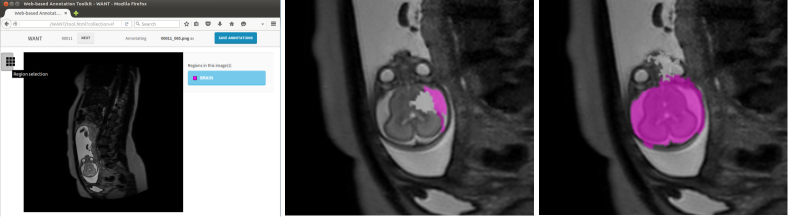

Refer to caption

Figure 1: Proposed crowdsourcing interface in a browser showing an uterine MR image from a stack of sagittal slices (left). Enlarged examples of progressing super-pixel annotations on the displayed images (middle and right).

For a flexible solicitation of annotation tasks, we propose a crowdsourcing platform where users can interact and annotate image data. To accelerate the annotation process, we provide a SLIC super-pixel segmentation [13] and let users select those belonging to the object we are interested in. We implement the SLIC computation using Javascript to outsource the computational load to the client machine and concentrate on backend tasks on the server side (e.g. data conversion, collection, etc.). The web-based user interface is based on the well-known LabelMe framework [11] and was modified to interact with volumetric medical image data and to compute and collect super-pixel annotations. Fig. 1 depicts the interface reduced to accommodate the particular annotation task at hand and an example of a user labelling super-pixel belonging to a fetal brain on a T2w MR image slice.